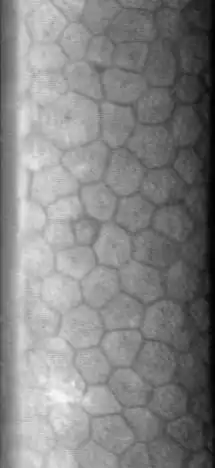

El endotelio corneal es una monocapa de células hexagonales que se encuentra situada en la superficie interna de la córnea, en contacto directo con el humor acuoso y la cámara anterior del ojo. Está formado por una única capa de células hexagonales de tamaño bastante uniforme, con un espesor que oscila entre 10 y 20 micras. Esta capa no tiene la capacidad de hacer mitosis, por lo cual no se regenera. Se comporta como una membrana semipermeable que permite el paso del humor acuoso a través suyo, el cual aporta glucosa y otros nutrientes al interior de la córnea, haciendo posible su nutrición. Por otra parte dispone de un mecanismo que transporta activamente el agua en sentido inverso, mediante gasto energético. Esta segunda propiedad es fundamental para evitar que la córnea se edematice —aumente de volumen por acumulación de agua—. En oftalmología es posible la visualización directa del endotelio corneal mediante un instrumento óptico llamado microscopio especular.[1] [2]

La microscopia especular permite la visualización del endotelio córneal en vivo, mostrando el tamaño la forma y densidad celular. La técnica se basa en proyectar un estrecho haz de luz sobre la córnea, con un determinado ángulo de incidencia, una pequeña fracción de la luz se refleja en la interface endotelio córneal - humor acuoso, como si se tratara de un espejo, y es recogida por el objetivo del microscopio, formando una imagen amplificada de la zona.[1]